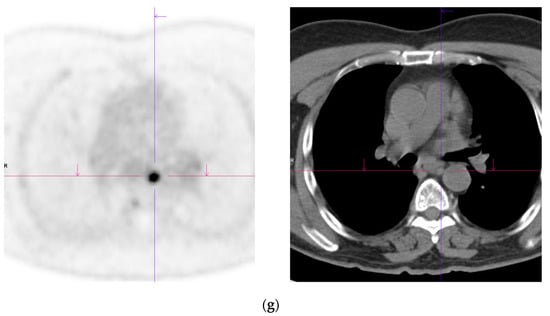

Figure 2.

Primary staging. 70 yr old M; PSA 42; Gleason 4 + 5 = 9; MR scan—PIRADS 6 at right apex; PIRADS 4 at left midzone. PSMA PET-CT: 68Ga-PSMA - 216 MBq; uptake 48 min; BMI = 30.5; Wt 83 Kg. (a): Coronal images—focal uptake midline apex anterior SUV = 26.1 with smaller focus SUV-5.4 right midzone; bulky disease in abdominal nodes; metastasis left humerus; left para-aortic node in thorax; bony metastasis left side of S1. (b,c): enlarged coronal and transaxial images of left common iliac/para-aortic nodal disease and uptake in apex of gland; transaxial images—node measures 14 mm SUV = 40.1; X-hairs show location. (d,e): enlarged coronal and transaxial images of right pelvic nodal that measures 1.4 mm SUV = 5.1; uptake in right midzone and apex as well as disease in left midzone of gland; X-hairs show location. (f,g): enlarged coronal images of para-aortic/para-oesophageal nodal disease in mediastinum; node measures 5.5 mm, SUV = 17.2; X-hairs show location.